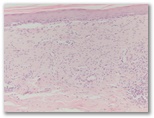

Diagnostico